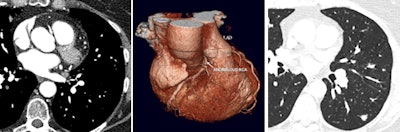

A case in point, van Beek remembers a CT scan that showed a right coronary artery anomaly (shown in figure below). He insisted on a reconstructed full field-of-view and discovered metastatic breast cancer, which changed management of the patient to extensive chemotherapy before coronary surgery. This also led to a shift in the cardiologist's mind at the time as to the usefulness of reconstructed full field-of-view images.

Patient presenting with suspected anomalous right coronary artery. Coronary CT angiography shows interarterial right coronary artery (left, also shown on 3D reconstruction in center). Full field-of-view reconstruction reveals spiculated lung lesion, which proved to be metastatic breast cancer (right). Images courtesy of Dr. Edwin van Beek, PhD.ECR 2016 delegates will also be reminded of the subtle information available on CT and MR such as abnormal shape (D-shaping) of the interventricular septum, which may indicate pulmonary pressure overload or how thickened interlobular septae and pulmonary ground-glass opacities on CT may point to pulmonary congestion secondary to heart failure.